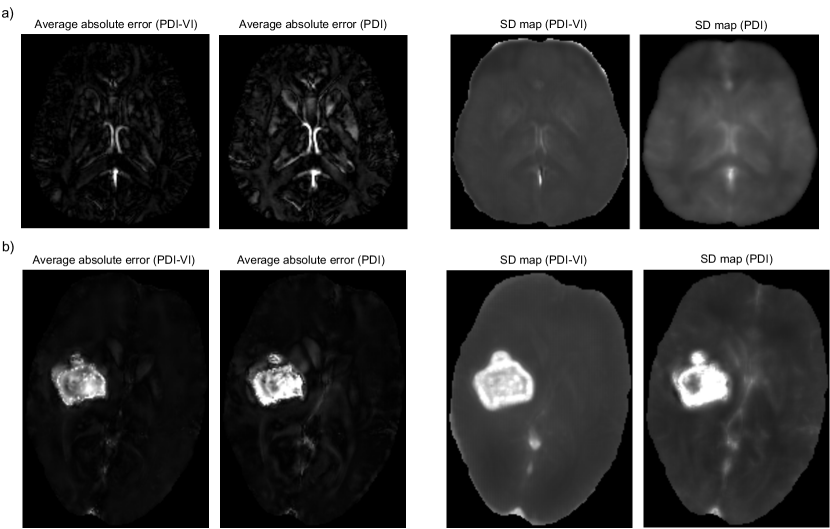

To evaluate uncertainty estimation performance of the predicted SD map, absolute error maps of PDI and PDI-VI’s mean predictions to the ground truth susceptibilities were computed via simulation, then correlation between susceptibility SD and error maps was examined. Local field inputs were simulated from (a) COSMOS test data in Figure 2 and (b) FINE reconstruction of the ICH patient in Figure 4a through multi-echo data synthesization with additive noise, nonlinear field fitting and phase unwrapping. Details of the simulation steps are shown in Appendix A. Such simulation was repeated 100 times to generate 100 local fields as inputs to PDI and PDI-VI. 100 mean maps of PDI and PDI-VI were predicted accordingly to compute the average absolute errors. Figure 7 shows the average absolute error maps and predicted SD maps of PDI and PDI-VI. In Figure 7a, large errors in the cerebral veins and sagittal sinus were reflected in the predicted SD maps for both PDI and PDI-VI, while in Figure 7b, large errors in the hemorrhage were also predicted in PDI and PDI-VI’s SD maps, which demonstrates good correlation between the error map and the predicted SD map of the proposed method for uncertainty estimation.